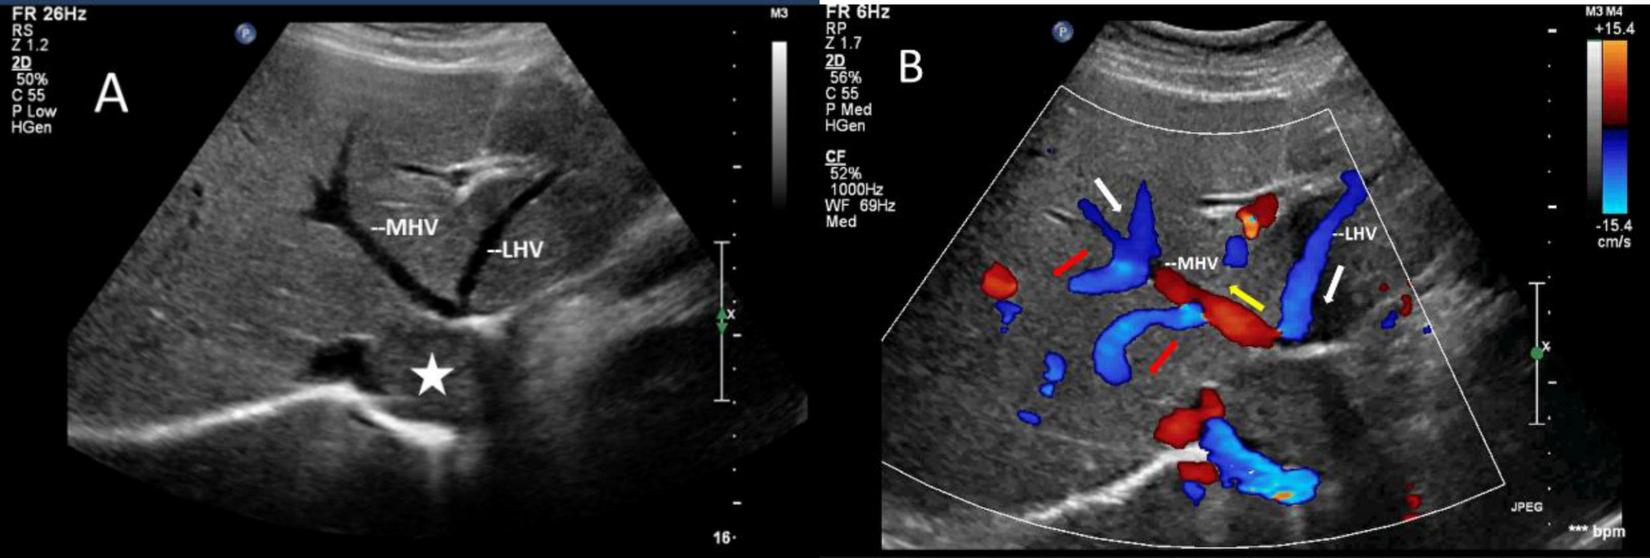

The mass can also be visualized within the right atrium and inferior vena cava using gray scale ultrasound imaging, appearing as a hypoechoic lesion of considerable length (Figure 3). Additionally, color Doppler ultrasonography can be utilized to assess hepatic vein obstruction and the direction of hepatic blood reflux. We can see that there is obstruction in the blood flow of the left and middle hepatic veins, resulting in a reversal of blood flow from the left hepatic vein into the middle hepatic vein (Figure 4). This obstruction has led to the formation of multiple collateral circulations between the middle hepatic vein and either the right hepatic vein or the dilated accessory hepatic vein in the posterior right lobe (Figure 5). These collateral circulations serve to drain the blood flow from the distal segment of the middle hepatic vein and the left hepatic vein into the inferior vena cava.

FIGURE 4

Images of liver greyscale and color Doppler sonography. (A) The lesion (asterisk) obstructed the blood flow from the left and middle hepatic veins to the inferior vena cava, resulting in a reversal of blood flow from the left hepatic vein into the middle hepatic vein. (B) Arrows show the direction of the blood flow: the white arrows illustrate the normal direction of blood flow, while the yellow arrows indicate the retrograde flow of the proximal segment of MHV, which drains LHV and redirects it through collateral vessels (red arrows) to the veins in the right lobe of the liver. LHV, left hepatic vein; MHV, middle hepatic vein.